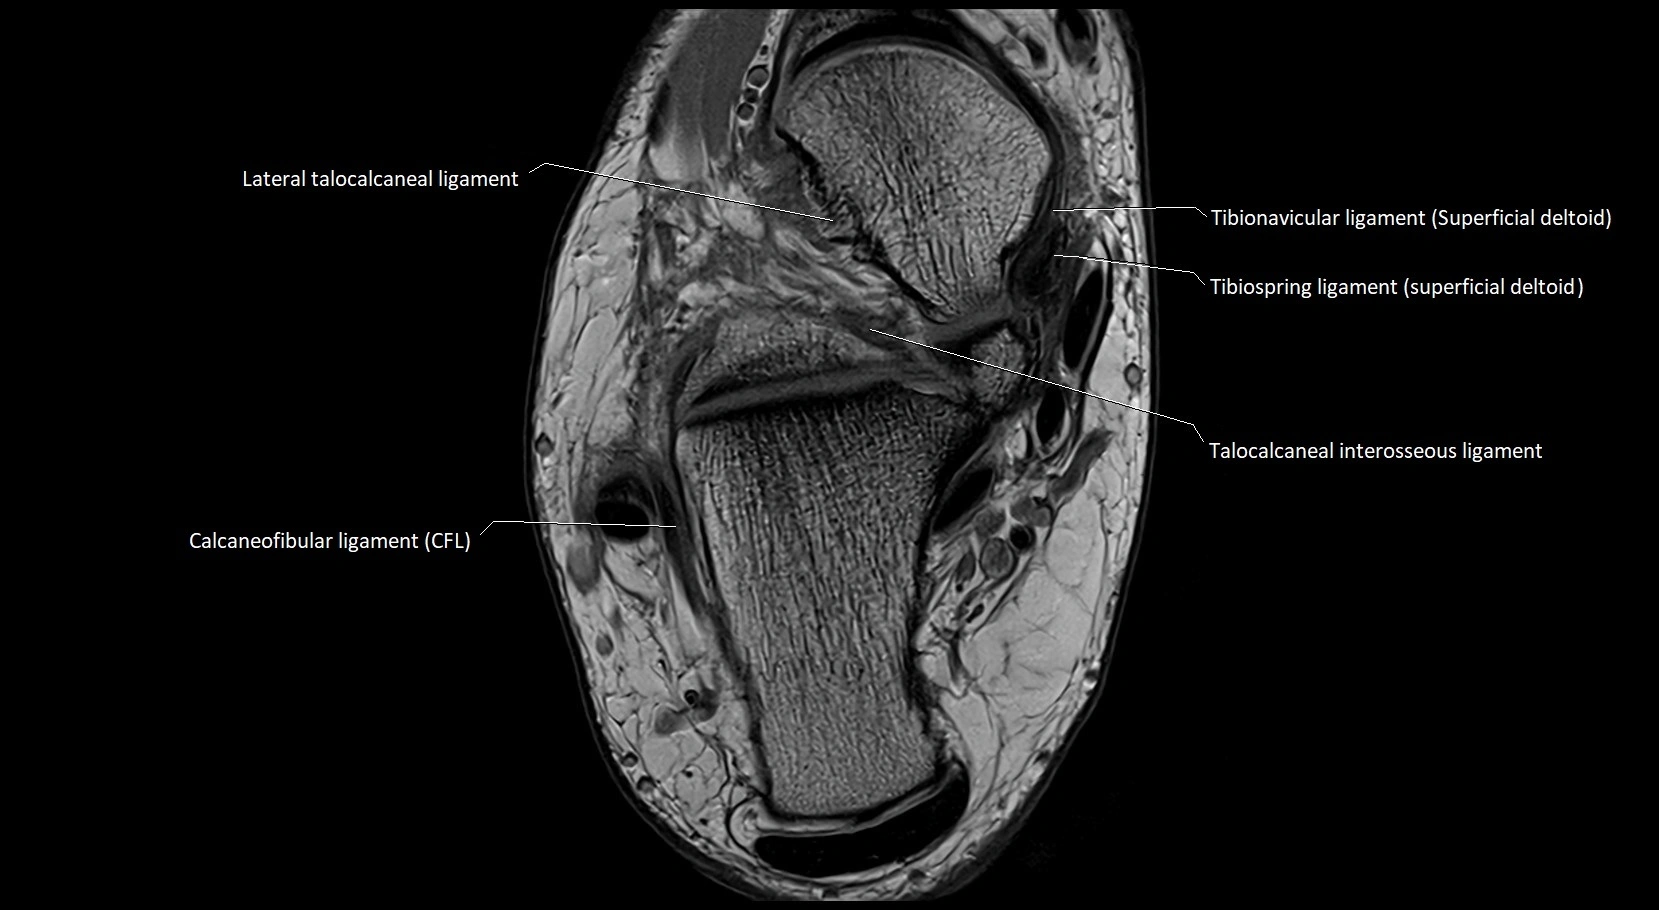

MRI image

image